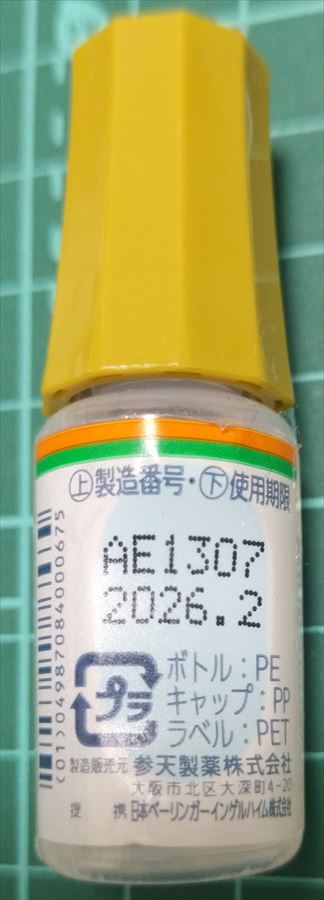

22.10.29 鼻炎薬吸引 モメタゾン点鼻液50μg 噴霧用 5mg10g 杏林 56噴霧用